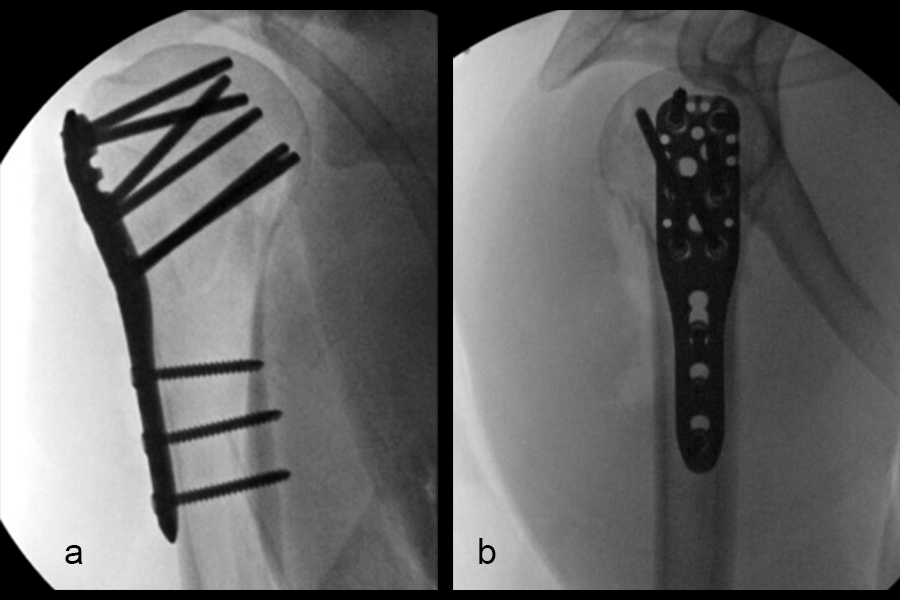

Definitive fixation was performed with a 3-hole VOLT™ Proximal Humerus plate (Fig 4). The plate was placed just beneath the rotator cuff insertion to directly support the greater tuberosity component. The proximal screws angulated toward the superior head to maximize length. The calcar screws were placed in a slightly splayed trajectory. One of the angular stable variable angled screws in the central portion was angulated in a posterior and more central position. This permitted maximal screw spread within the humeral head.

Three months after surgery, the patient had good elevation in the scapular plane to 130 degrees. External rotation was measured at 30 degrees, with more limited internal rotation (to the belt line). X-ray imaging (Fig 5) showed maintenance of fracture alignment and no change in screw position. The axial view (Fig 5c) highlights the subchrondral position of the variable angular screws in the humeral head. The patient was progressing nicely with functional tasks and adding weight in her therapy program.